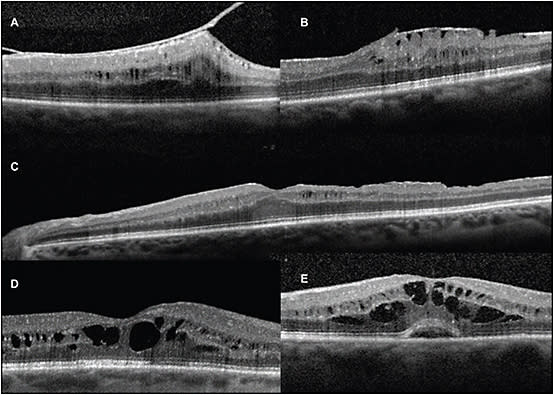

A challenge arises in differentiating edema from nonvasogenic forms of cystic change, such as those that occur secondary to vitreomacular pathology. In the author’s experience, purely structural cystic spaces demonstrate an inner retinal surface contour abnormality, such as epimacular membrane, VMT, clear previous epiretinal surgical trauma, or altered foveal anatomy as demonstrated in Figure 2. One exception to this notion is the acquired emmetropic macular schisis that remains stable with OPL morphology on SD-OCT and has little effect on visual acuity.

Figure 2. Differentiating SD-OCT features of structural retinal cystic changes and macular edema. A) Inner nuclear layer (INL) cystic changes within a region of epimacular membrane and vitreomacular traction and inner retinal contour abnormality. B) INL cystic changes underlying area of epimacular membrane. C) Delayed-onset INL cystic changes appearing three months following membrane scraper trauma. D) Typical two- and (E) three-layer cystoid macular edema with combined INL and outer plexiform morphology in addition to subretinal fluid.